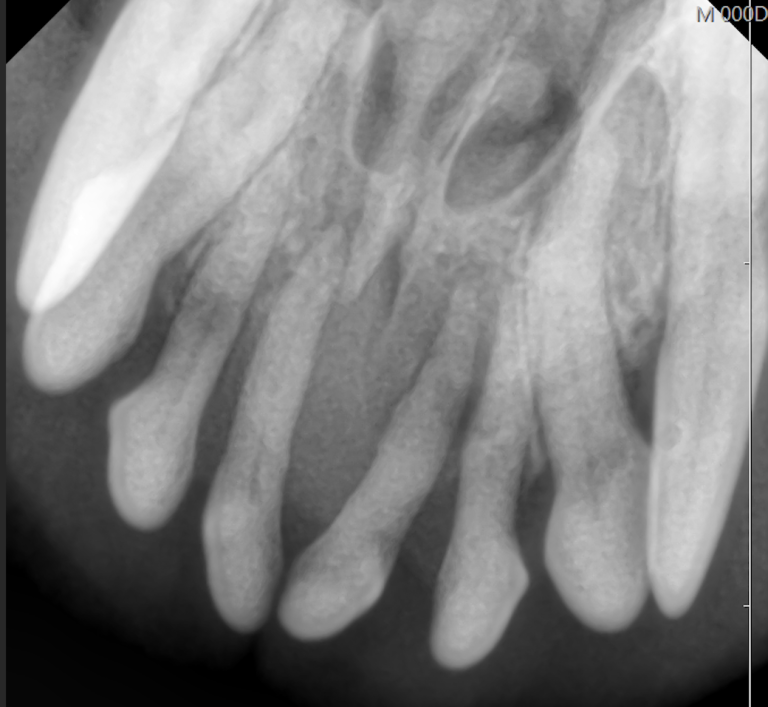

下の写真を見てみましょう。

全臼歯抜歯を行った症例の抜歯後1ヶ月の写真です。

手術前に腫れていた歯肉や口腔粘膜の状態も改善しました。

手術後食欲も増え、体重も増加しました。